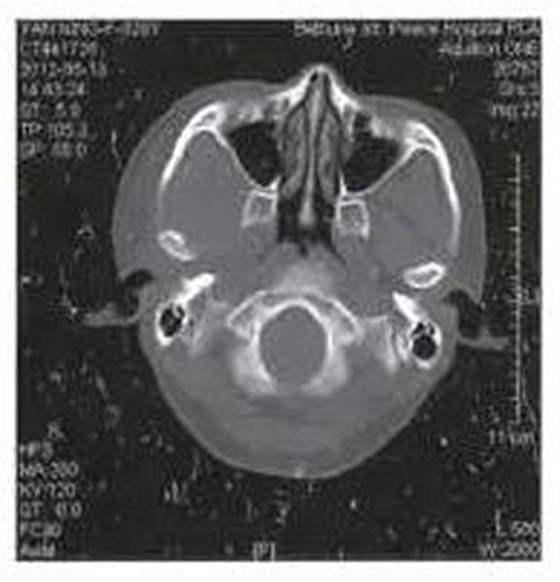

病例2,女,28歲。于1月前拔除右側(cè)上頜第三磨牙,3天后出現(xiàn)右側(cè)顳部劇烈疼痛,張口度15 mm,經(jīng)多家醫(yī)院保守治療效果不佳。CT掃描顯示右側(cè)咬肌及顳下間隙軟組織腫脹,右側(cè)髁突內(nèi)側(cè)有少量死骨形成(圖2)。入院后全麻下采用口內(nèi)入路手術(shù),刮除死骨,引流膿液,放置引流條。術(shù)后1月復(fù)查,張口度達(dá)到25 mm。

圖2右側(cè)髁突骨髓炎,死骨形成